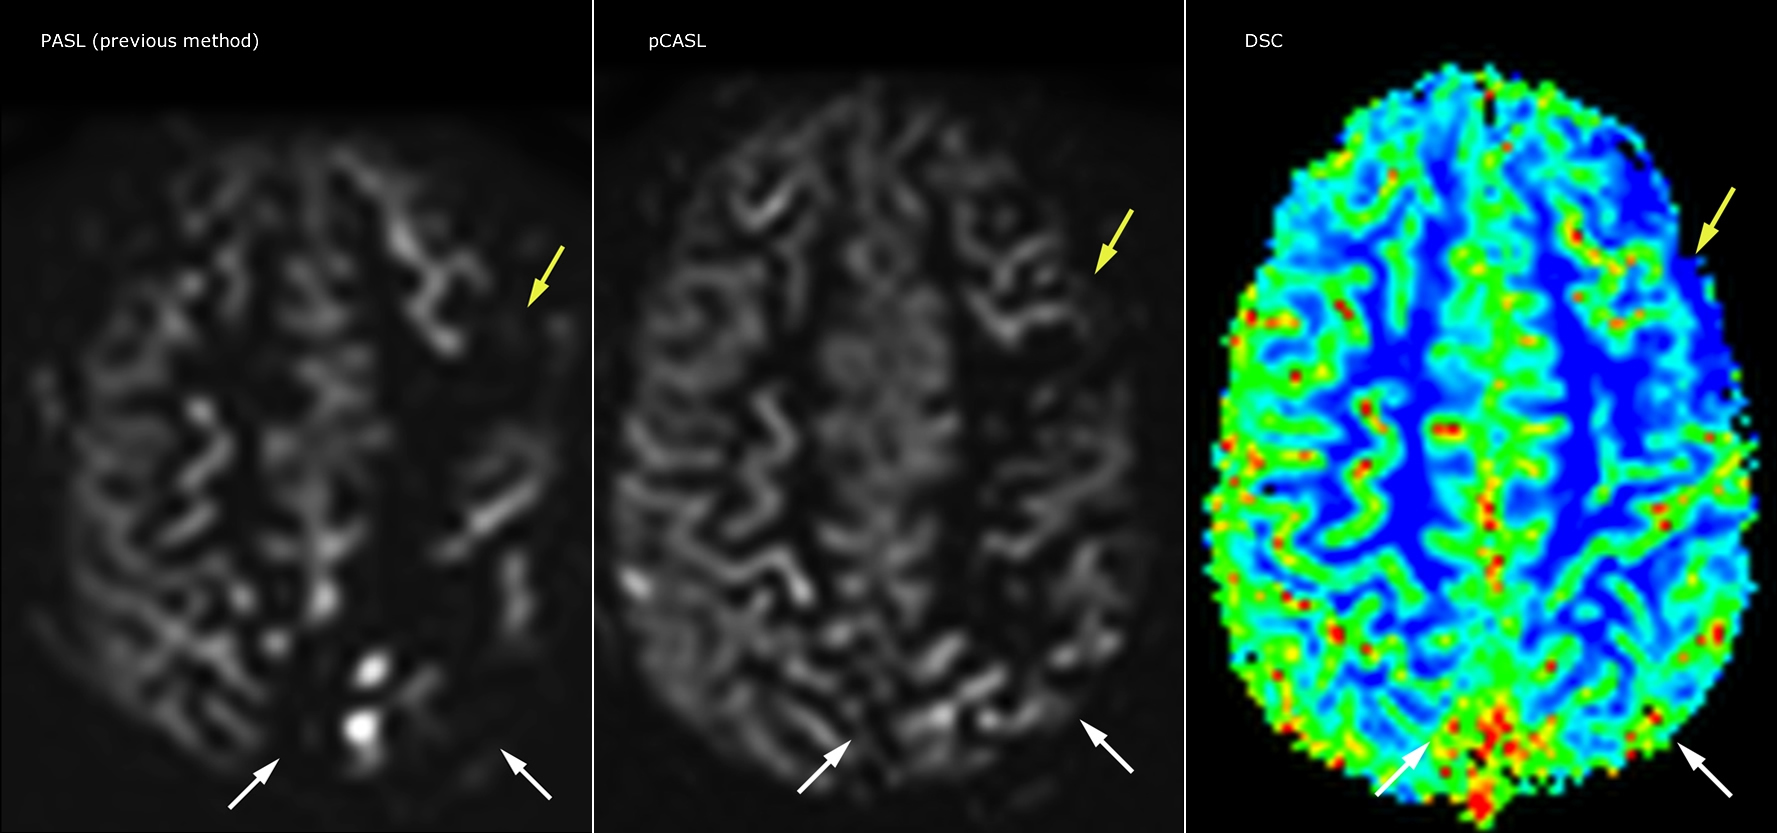

Pseudo-continuous arterial spin labeling (pCASL) was developed for brain perfusion imaging without contrast agent. “This is very desirable in pediatric patients where the general trend is to limit the administration of contrast,” says Dr. Miller.

Dr. Miller uses pCASL for all patients who present with chronic and acute cerebrovascular abnormalities such as acute stroke, as well as patients who present with signs of acute inflammation in the brain, and occasionally in patients with tumors, to assess the perfusion status of their tumor.

“In combination with diffusion weighted imaging, it can help give a more extended assessment of the degree of perfusion abnormality in a patient who is suffering acute ischemia. We have a number of patients who have chronic arterial insufficiency due to prior arterial abnormalities or acquired arterial abnormalities such as sickle cell disease or neurofibromatosis. Sometimes the child’s first manifestation of disease progression is a reduction in brain perfusion before stroke symptoms manifest clinically or in diffusion weighted imaging. We use pCASL to help delineate the perfusion abnormality.”

Growing confidence in specific applications

“We built up confidence in pCASL by comparing it to contrast-based perfusion imaging. Once we had confidence that it was representing what the contrast perfusions were representing, we increased our diagnostic confidence by serial imaging in either the acute stage or the long term stages in a number of patients with arterial abnormalities.

To other new users I would recommend to also start to interpret the pCASL images in comparison with other standard imaging – T2 and FLAIR and DWI – until the user gains confidence in interpreting these images by themselves.”

“A powerful use of pCASL is in patients with chronic cerebrovascular stenosis, where clinicians desire information on how compensatory mechanisms of the brain are performing to enable perfusion to the brain. Often clinicians take into account how the compensatory mechanisms appear to help to provide adequate perfusion to the patient’s brain, and they may intervene surgically or make some other management decision.”

Efficiencies gained with pCASL

“pCASL has now become more of a first-line scan for assessing perfusion for us, as opposed to DSC-based perfusion imaging with contrast agent. And in patients who were not planned to have contrast, we can perform pCASL for perfusion imaging without need to stop the exam, pull the patient out, and put in an IV. It also negates the postprocessing that’s necessary for dynamic susceptibility contrasts. And it allows us to repeat perfusion imaging in the same patient at the same imaging time, which is helpful in terms of patient motion, or in a situation where a scan needs to be done before pharmacological perfusion imaging.”